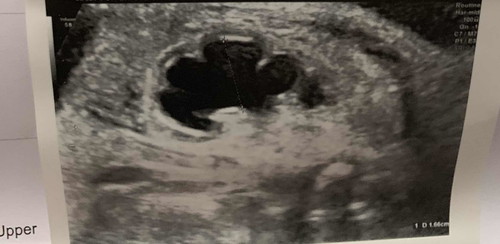

ถุงน้ำในไตน้อง ตอนอยู่ในครรภ์

สวัสดีค่ะแม่ๆ ใครมีประสบการณ์ ตั้งครรภ์ แล้วซาวน์เจอ ถุงน้ำในไตน้องบ้างค่ะ วันนี้แม่อายุครรภ์ 35+4 w ซาวน์ดูน้อง ปรากฎว่า หมอบอกว่าในไตน้องเหมือนมีถุงน้ำอยู่ ปกติซาวน์ทุกครั้งแต่ไม่เคยเห็น อาจจะเพราะน้องไม่ได้อยู่ในท่าที่ให้เห็นค่ะ แต่วันนี้เห็น แม่ถามหมอว่าเกิดจากอะไร หมอบอกว่าน่าจะเป็นท่ออะไรสักอย่าง ตีบตัน หรือเล็กประมานนี้ค่ะ หมอนัดซาวน์เพื่อความแน่ใจอีกครั้ง ห้องซาวน์ใหญ่ อยากรู้ว่ามีแม่ๆคนใหนเคยเจอแบบนี้บ้างค่ะ แล้วน้องออกมาเป็นยังไง ร้ายแรงมั้ย และมีวิธีรักษายัง แม่กังวลมากเลยค่ะตอนนี้ ช่วยแนะนำหน่อยค่ะ